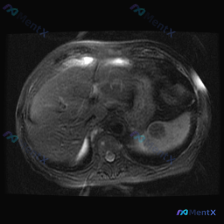

整理了一份有点意思的读片分析,核心是“关注点错位”——临床问的是脾脏病变,但影像的真正异常在肝脏。 一、先看影像基础信息 - 序列:腹部MRI轴位T1加权像 - 覆盖范围:上腹部(肝左/右叶部分、脾脏、胰腺体尾、胃泡、腹主动脉) - 图像质量:信噪比良好,无明显运动伪影 二、关键影像表现(按事实优先...

看到一份腹部MRI的读片资料,病灶在脾脏,整理一下思路分享给大家。 病例影像核心信息 - 影像类型:腹部MRI T2加权序列(T2WI),轴位 - 主要发现:脾脏边缘可见数个小类圆形高信号灶(点状高亮),呈水样信号,边界锐利、边缘光整 - 其他结构:肝实质信号相对均一,未见明确占位;胰腺体尾部形态、...

最近看到一份读片资料,提问是“观察脾脏病变”,但仔细看完影像和分析后,觉得这个病例的思维转折比诊断本身更有价值,整理一下思路和大家分享。 --- 先看核心影像事实(基于MRI-T2轴位) 这份图像的基本信息很明确:上腹部轴位T2加权像,有轻度呼吸伪影但不影响评估。 直接说关键的阳性/阴性发现: ✅...

今天整理了一个很有意思的“反向”影像分析案例,核心不是鉴别病变性质,而是先搞清楚“病变到底存不存在”——这个前提如果错了,后面的分析全是浪费时间。 先看一下当前的资料 临床提示:脾脏病变 影像资料:单帧腹部MRI T2序列轴位图像 影像客观描述: - 肝脏:轮廓尚可,实质信号基本均匀,未见明确局灶性...

整理了一份脾脏占位的读片+分析思路,感觉这个病例的「混杂信号」挺有代表性,容易被带偏,分享出来一起理一理。 --- 一、先看影像核心表现 这份是上腹部MRI轴位T2加权像: - 肝脏、胃壁、腹膜后大血管这些都还好,没见明显异常; - 脾脏形态正常,但里面有一个类圆形占位,边界尚清; - 关键信号:T...